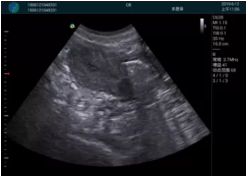

M20便攜超聲在臨床中的應(yīng)用:

可視化穿刺引導(dǎo)

M20實時引導(dǎo):向包塊后方間隙注射利多卡因

便攜超聲引導(dǎo)下人流術(shù)

病例一:

清晰顯示孕囊,通過軟件包計算孕齡7w+6d

M20實時引導(dǎo),術(shù)中清晰顯示孕囊被破壞和抽吸針的過程,清晰顯示吸引針

抽吸結(jié)束后縱切子宮,孕囊已被完全抽吸,未見明顯殘留

橫切子宮,發(fā)現(xiàn)右側(cè)宮腔靠近宮角處有少許脫模樣殘留

M20引導(dǎo)下,抽吸針找到右側(cè)宮角處再次清掃

二次抽吸后再次進行超聲檢查,宮腔未見殘留,宮腔線清晰顯示

超聲引導(dǎo)下可視化人流是技術(shù)安全性的保障,一般對人流術(shù)設(shè)備預(yù)算不高,M20具備婦產(chǎn)科軟件包,且穿透力圖像質(zhì)量好,既滿足人流引導(dǎo)需要,也可用于床旁超聲的需求。